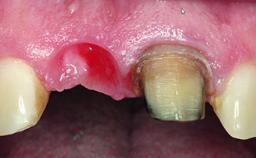

A healthy 37-year-old female patient was referred for a consultation on the replacement of missing tooth 21 with an implant-supported restoration. She stated that several years previously the tooth had been traumatically avulsed following a motor vehicle accident. The tooth was replaced with a three-unit fixed partial denture (FPD) immediately afterwards. Over time, she became disillusioned with the FPD and looked for a different option, including orthodontic therapy. She presented still in her orthodontic appliances, with the pontic sectioned free from the FPD but attached to the archwire. Her orthodontist felt that orthodontic treatment had been successfully completed, but nevertheless referred her before removing the appliances in case adjustments were necessary.

Soft Tissue Anatomy Intact Defective

Bone Volume Horizontally and vertically sufficient Horizontally deficient Deficient vertically or deficient vertically AND horizontally

Soft Tissue Contour and Volume Slightly compromised